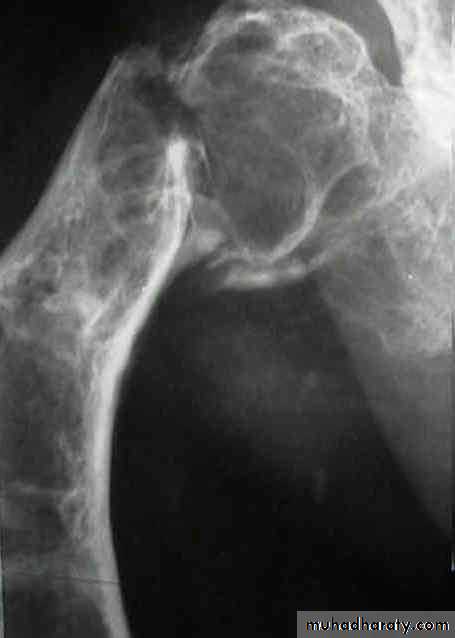

Developmental disorder whereby normal bone is replaced by fibrous tissue with flecks of osteoid.It may affect one bone (monostotic) or multiple bones (polystotic).

The lesion may be very large causes bone expansion and cortical thinning with progressive deformity and sometimes pathological fracture.Lesions occur in metaphysis & diaphysis, proximal femur is a common site it gives characteristic deformity called (shepherd’s-crock deformity(عصا الراعي.

X-ray shows lucent cystic lesion sometimes large and multilocular with bone expansion and cortical thinning it contains multiple calcific spots giving the ground-glass appearance, there is always possible deformity or pathological fracture.